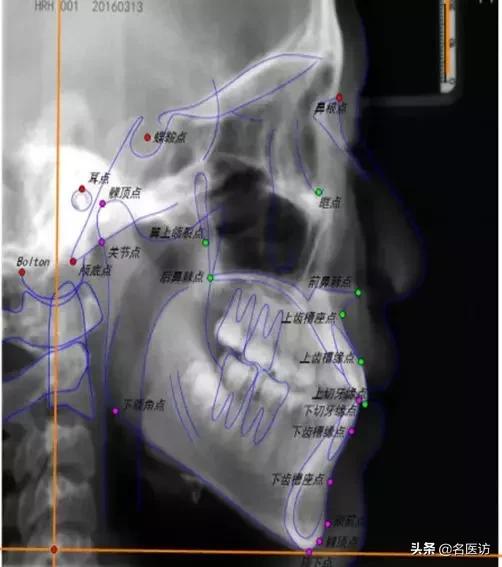

矫正前后的侧位片,可以帮助医生了解牙齿、颌骨的状态及变化情况,并进行侧貌的美学评估。

侧位片(图片来自影像园网,侵删)

医生会用很多标志点和平面来分析侧位片,天使君很难将所有的点一次跟天使er们介绍清楚。这次来跟天使君一起了解下几个常用的侧貌美学分析依据。

1、评估面型:SNA角

面型可粗略的分为3大类:直面型、凸面型、凹面型。其中,直面型是公认的最符合审美的面型,SNA角可以帮助我们了解自己的面型和凹凸度。

N:鼻根点,鼻额缝的最前点

S:蝶鞍点,蝶鞍影响的中心

A:上牙槽座点,鼻子和上牙槽接触的最凹点

当该角过大时上颌前突,面部侧貌呈凸面型;反之上颌后缩,面部呈凹面型。

2、评估下颌位置:SNB角

B:下牙槽座点,下牙槽和颏部接触的最凹点

当该角过大时下颌相对前颅底的位置前突;反之呈颌后缩。

3、U1-SN

U1:上中切牙切缘点

反映上中切牙(俗称门牙)相对于颅底的倾斜度,角度越大,门牙越突,也就越可能出现龅牙的侧貌。

4、评估上下唇凸度:E线

Prn:鼻部最凸点

Pog’:颏部最前点

E线也叫审美平面,是鼻子凸点和颏前点的切线,用来评估上下唇的凸度。据统计,中国成年人上下唇超出E线的占76%,而美丽的成年女性,双唇应该都在E线内。(手动微笑再见!)